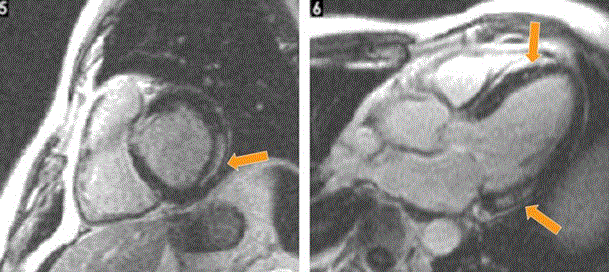

Magnetic resonance imaging

Cardiac magnetic resonance imaging (MRI) assess myocardial structure and function to provide useful information – LV mass, volume and contractility, myocardial strain analysis, tissue mapping and extracellular volumes – for the diagnosis of RCM [89]. Cardiac MRI is frequently used to assess myocardial interstitium and has high accuracy in detecting abnormal morphological factors in cardiac amyloidosis [87]. Recent findings suggest contrast (gadolinium) enhanced cardiac MRI reveals a characteristic pattern in sub-endocardium and abnormal myocardial kinetics. For instance, Figure 6 shows late gadolinium enhanced cardiac MRI image of a patient with RCM, short-axis (left) and apical 4-chamber view (right). The arrows indicate regions of local intra-myocardial brightness indicating intra-myocardial fibrosis.

Figure 6: Cardiac MRI with Delayed Gadolinium Enhancement

Cardiac MRI with delayed gadolinium enhancement in short axis (left) and apical 4-chamber (right) revealing localized intramyocardial brightness (arrows) suggesting intramyocardial fibrosis. Adapted from Nihoyannopoulos & Dawson, 2009, p. iii29 [5].